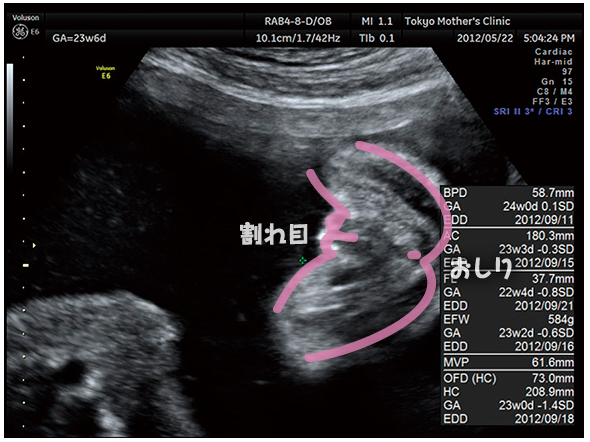

質問 Itmedia 22週目エコー写真での胎児の性別判断